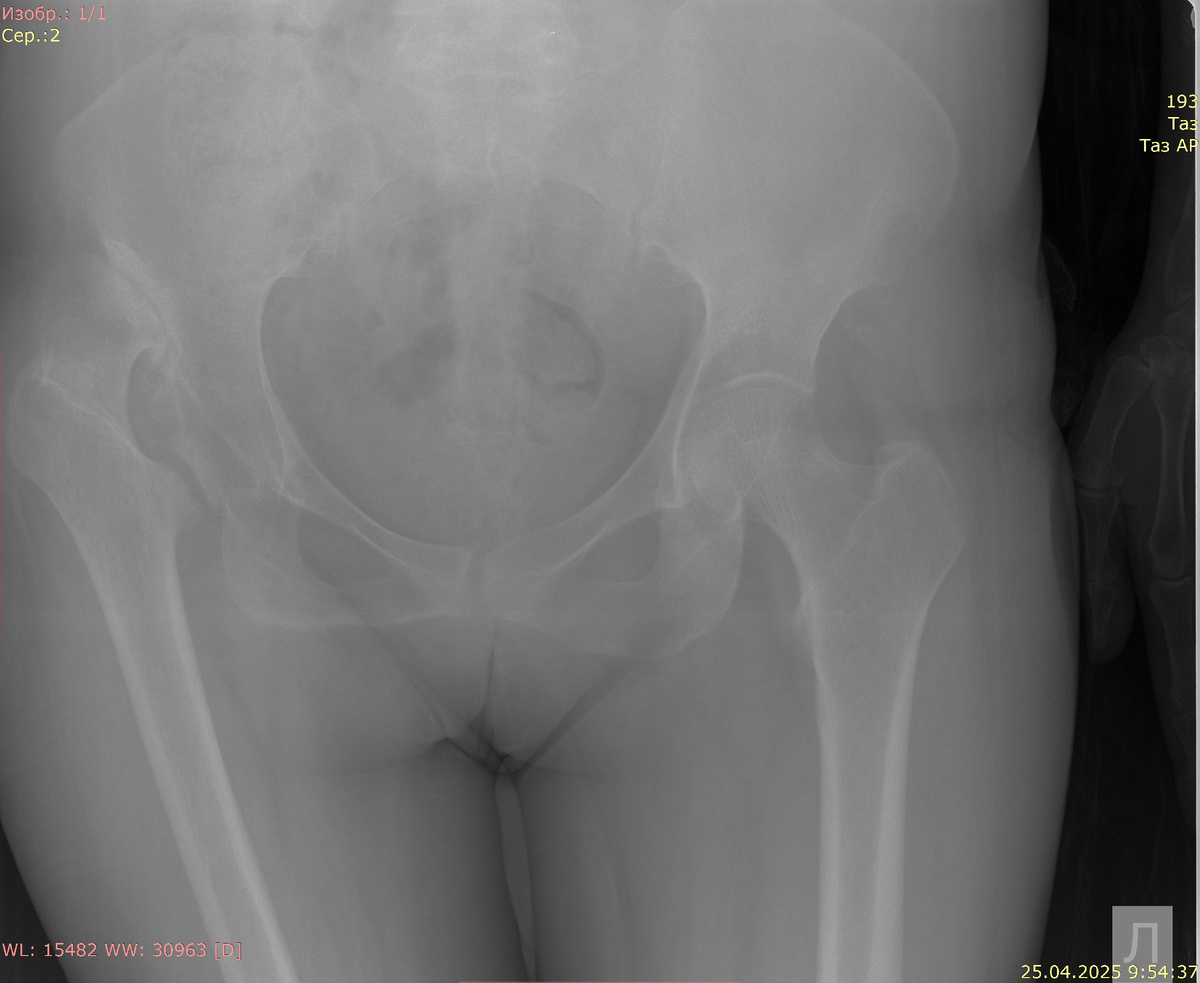

Рентгенография обоих тазобедренных суставов в прямой проекции:

Полный вывих правой бедренной кости на 7 см кверху. Остеосклероз подвздошной кости в месте соприкосновения с бедренной костью справа. Головка правой бедренной кости уплощена, с остеофитами. Кортикальная пластинка в видимых отделах костей непрерывна. Костная плотность и трабекулярная структура в видимых костях сохранена.

Заключение: старый вывих правой бедренной кости в т/б суставе.